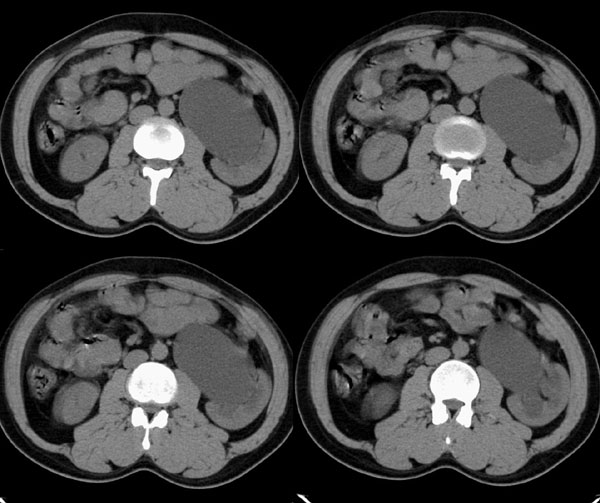

m29y平常体健,无明显不适。单位体检时发现左肾区病变。来我院作ct如下(病人不做增强):

左肾区囊肿冠、矢状重建: